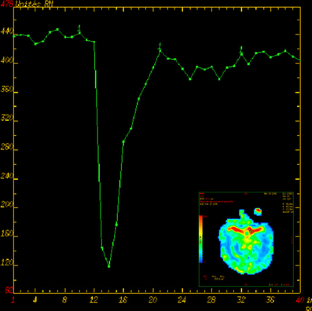

Cerebral perfusion-weighted imaging (PWI) in neonates is known to be technically difficult and there are very few published studies on its use in preterm infants. In this paper, we describe one convenient method to perform PWI in neonates, a method only recently used in newborns. A device was used to manually inject gadolinium contrast material intravenously in an easy, quick and reproducible way. We studied 28 newborn infants, with various gestational ages and weights, including both normal infants and those suffering from different brain pathologies. A signal intensity–time curve was obtained for each infant, allowing us to build perfusion maps. This technique offered a fast and easy method to manually inject a bolus gadolinium contrast material, which is essential in performing PWI in neonates. Cerebral PWI is technically feasible and reproducible in neonates of various gestational age and with various pathologies.

Fig. 1

Fig. 2

Fig. 3